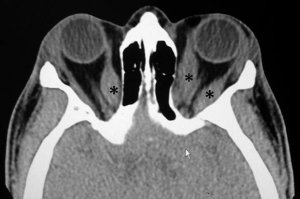

Computed tomography (CT) scan: This type of imaging without contrast may distinguish normal structures from abnormal structures of different tissue density. It demonstrates enlargement of the bellies and sparing of the tendons. It helps in assessing the relationship between the optic nerve and muscles at the apex, which helps in planning for the surgical intervention, if needed.